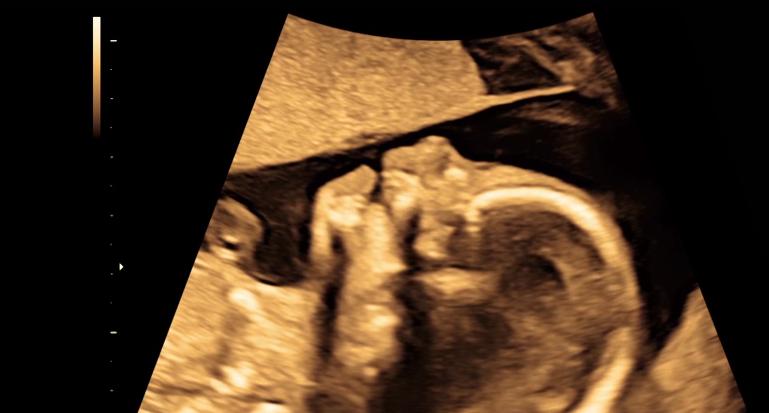

怀孕19周的贝基和丈夫来到医院进行产检,看着B超投影仪上女儿清晰的侧面轮廓她幸福极了。

然而当她看到赫然出现的巨大肿瘤时,贝基难过的情绪瞬间涌现,如果再不进行手术,那么胎儿很可能会出现心力衰竭最终胎死腹中。

巴斯基医生只能依靠模糊的B超投影仪来寻找肿瘤的位置,尽管如此,他还是凭借丰富的经验将针管快狠准地扎进了准确位置,接着激光纤维的导入也很顺利,巴斯基医生没有丝毫犹豫,迅速找到了供血管的位置并利用激光堵住了它,不一会B超显示胎儿正在向胎盘泵血了,这就意味着手术结果的顺利和成功,巴斯基医生的沉稳操作甚至让肚子里的胎儿没有察觉到任何异常,听到这个天大的好消息,贝基和丈夫都喜极而泣,现在,她的女儿终于可以平安长大了。